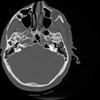

4 CEREBRO,,Vol,0.5,CEREBRO,,